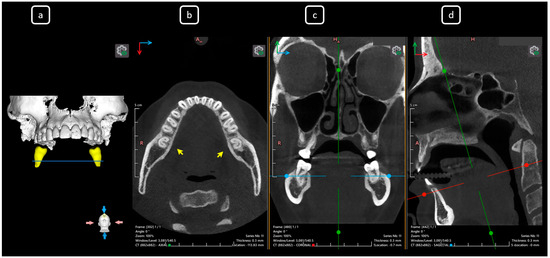

Cone beam computed tomography (CBCT) is a valuable diagnostic tool for evaluating the upper airway and maxillofacial region. This report demonstrates the clinical value of CBCT in identifying significant anatomical variations in endodontics, incidentally detected on a non-endodontic CBCT scan. A 23-year-old female patient underwent CBCT imaging at the Faculty of Dentistry-UJED to evaluate her upper airway. CBCT imaging revealed a unique, complex, and unusual anatomy of mandibular root canals, characterized by Vertucci’s type III root canals in the anterior sextant and co-occurrence of bilateral C-shaped mandibular second molars (type C2 according to Fan’s classification). No therapeutic interventions were initiated due to the patient’s asymptomatic status. CBCT imaging is a valuable tool for integrated diagnostic approaches, underscoring its role in thorough patient management. The integration of multidisciplinary interpretation of CBCT data can enhance diagnostic accuracy and optimize patient records and management, emphasizing the importance of collaborative efforts between radiologists, clinicians, and endodontists. Documenting and sharing such findings can increase awareness of rare anatomical variations, facilitating detection and contributing to medical knowledge. Full article

Figure 1